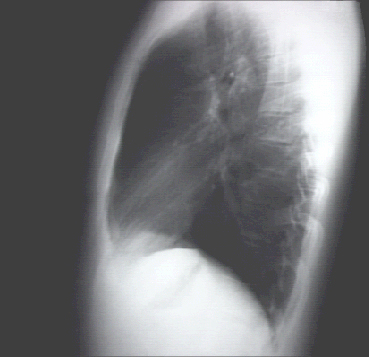

Your choice: Normal Lat View

This chest X ray is normal. The lateral view demonstrates normal dorsal kyphosis and no decrease in the anteroposterior diameter.